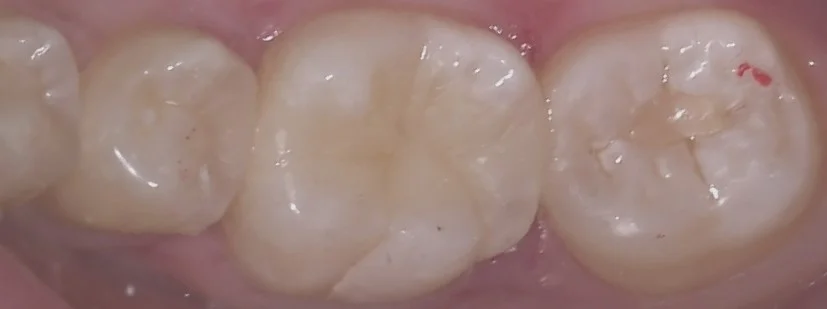

そして詰め終わったのがこちらです。

歯の表層のエナメル質と呼ばれる部分が乾燥のため白くなっており、色の違いが分かりやすくはなっていますが、1週間もしない内にエナメル質に水分が戻り、違和感が消えてきます。

適合はしっかりと合わせているので、割れたり欠けたりしなければそのまま使っていただけると思います。